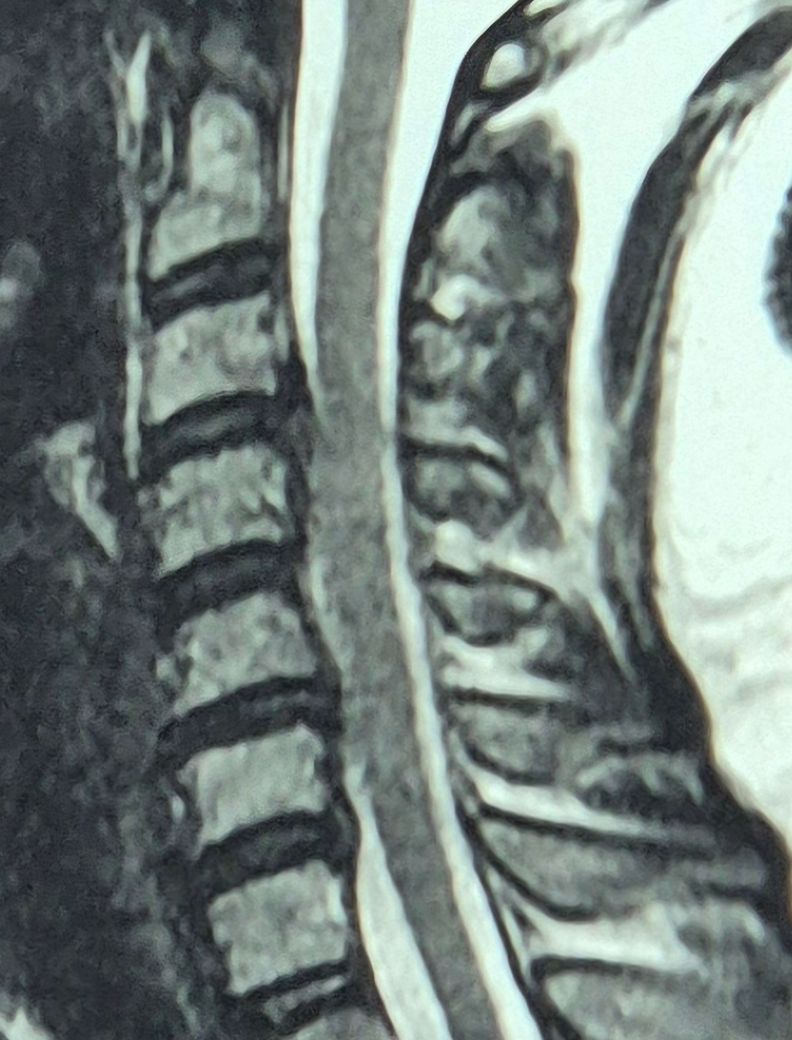

목디스크 어깨팔통증 질문드립니다!

2주가량 잠못들정도의고통..ㅠㅠ 오른쪽팔과어깨통증이있는데 mri 찍고 목디스크판정받았는데...병원에선 초음파로목에직접적으로 주사를넣지않고...주변신경차단주사를넣더라구요...그리고한3일째때

통증은덜해졌는데..오늘은 오른쪽이안아프고왼쪽팔이아픕니다..원래왼쪽은멀쩡했거든요..

근데 mri결과가 34번은왼쪽 56번은오른쪽으로

총디스크가4.개가나왓엇는데왼쪽통증은전혀없었는데 34번디스크가또신경을 누르고있는걸까요?..

• 1번 째 사진

이미 결과가 나온 MRI 영상이지만 어떤지 제2의 의견을 물어보시는거라면 이건 영상의학과 전문의에게 의견을 구하셔야 합니다.

영상 제외 말씀하신 증상 관련에 한해 답변 드리자면 목 디스크로 인한 통증이 오른쪽에서 왼쪽으로 옮겨가는 경우도 있을 수 있습니다.

주사를 맞은 후 구역질, 구토, 수면 장애 같은 증상이 발생했다면, 스테로이드 성분이 포함된 약물이 원인일 수 있으며, 부작용으로 그런 증상이 나타날 수 있죠. 주사를 맞고 상태가 더 악화되었다면 병원에서 추가적인 진료를 받는 것이 좋습니다만, 그 후에도 후처치가 좋지 않으면 병원 옮기시는 것도 괜찮습니다.

디스크 관련 증상은 사람마다 다르지만 환자분의 경우 여러 디스크가 관여하고 있어 신경계의 영향을 받는 경우 통증이 심할 수 있습니다. 현재 병원에서 제시한 치료 방법에 대한 불만이나 우려가 있다면 다른 병원에서 진료 받아보시고 제2의 의견을 구하시는 방법도 있습니다.